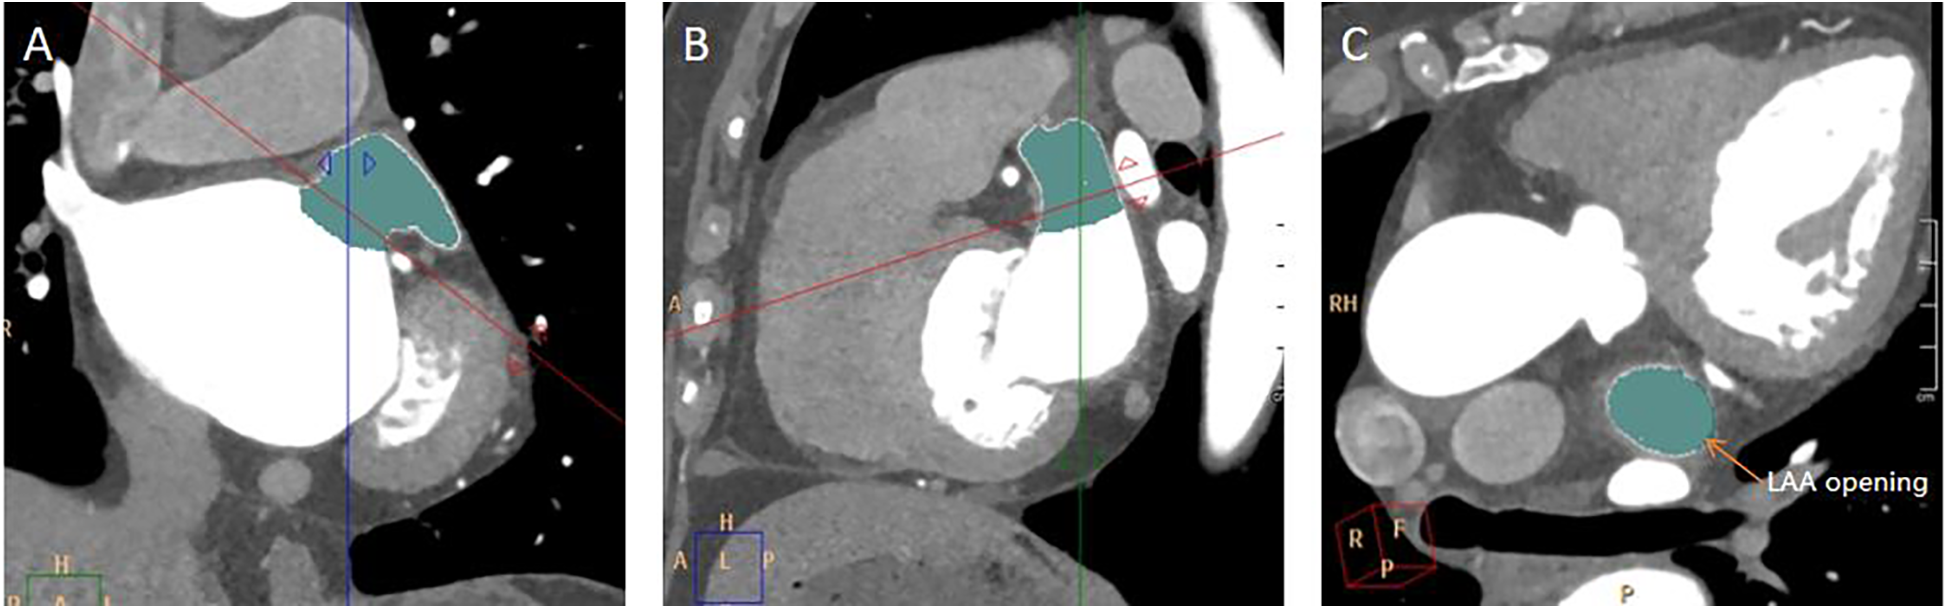

The long diameter, short diameter, area, and circumference of the opening of the LAA were measured. Find the maximum plane at the junction of the LAA and the LA in the coronal plane, perpendicular the positioning line to the junction of the LAA and the LA (Figure 2A). Then, on the sagittal plane image, perpendicular the positioning line to the junction of the LAA and the LA (Figure 2B). Utilizing the MPR technique and finally a cross-sectional image of the LAA opening was obtained (Figure 2C). The long diameter, short diameter, area, and circumference of the LAA base opening were measured on this cross-sectional image of the LAA opening (Figure 3).

Figure 2

Measurement of LAA opening. (A) A coronal image of the LAA opening. The red line was along the plane of the LAA opening. (B) A sagittal image of the LAA opening. (C) A transverse image of the LAA opening.